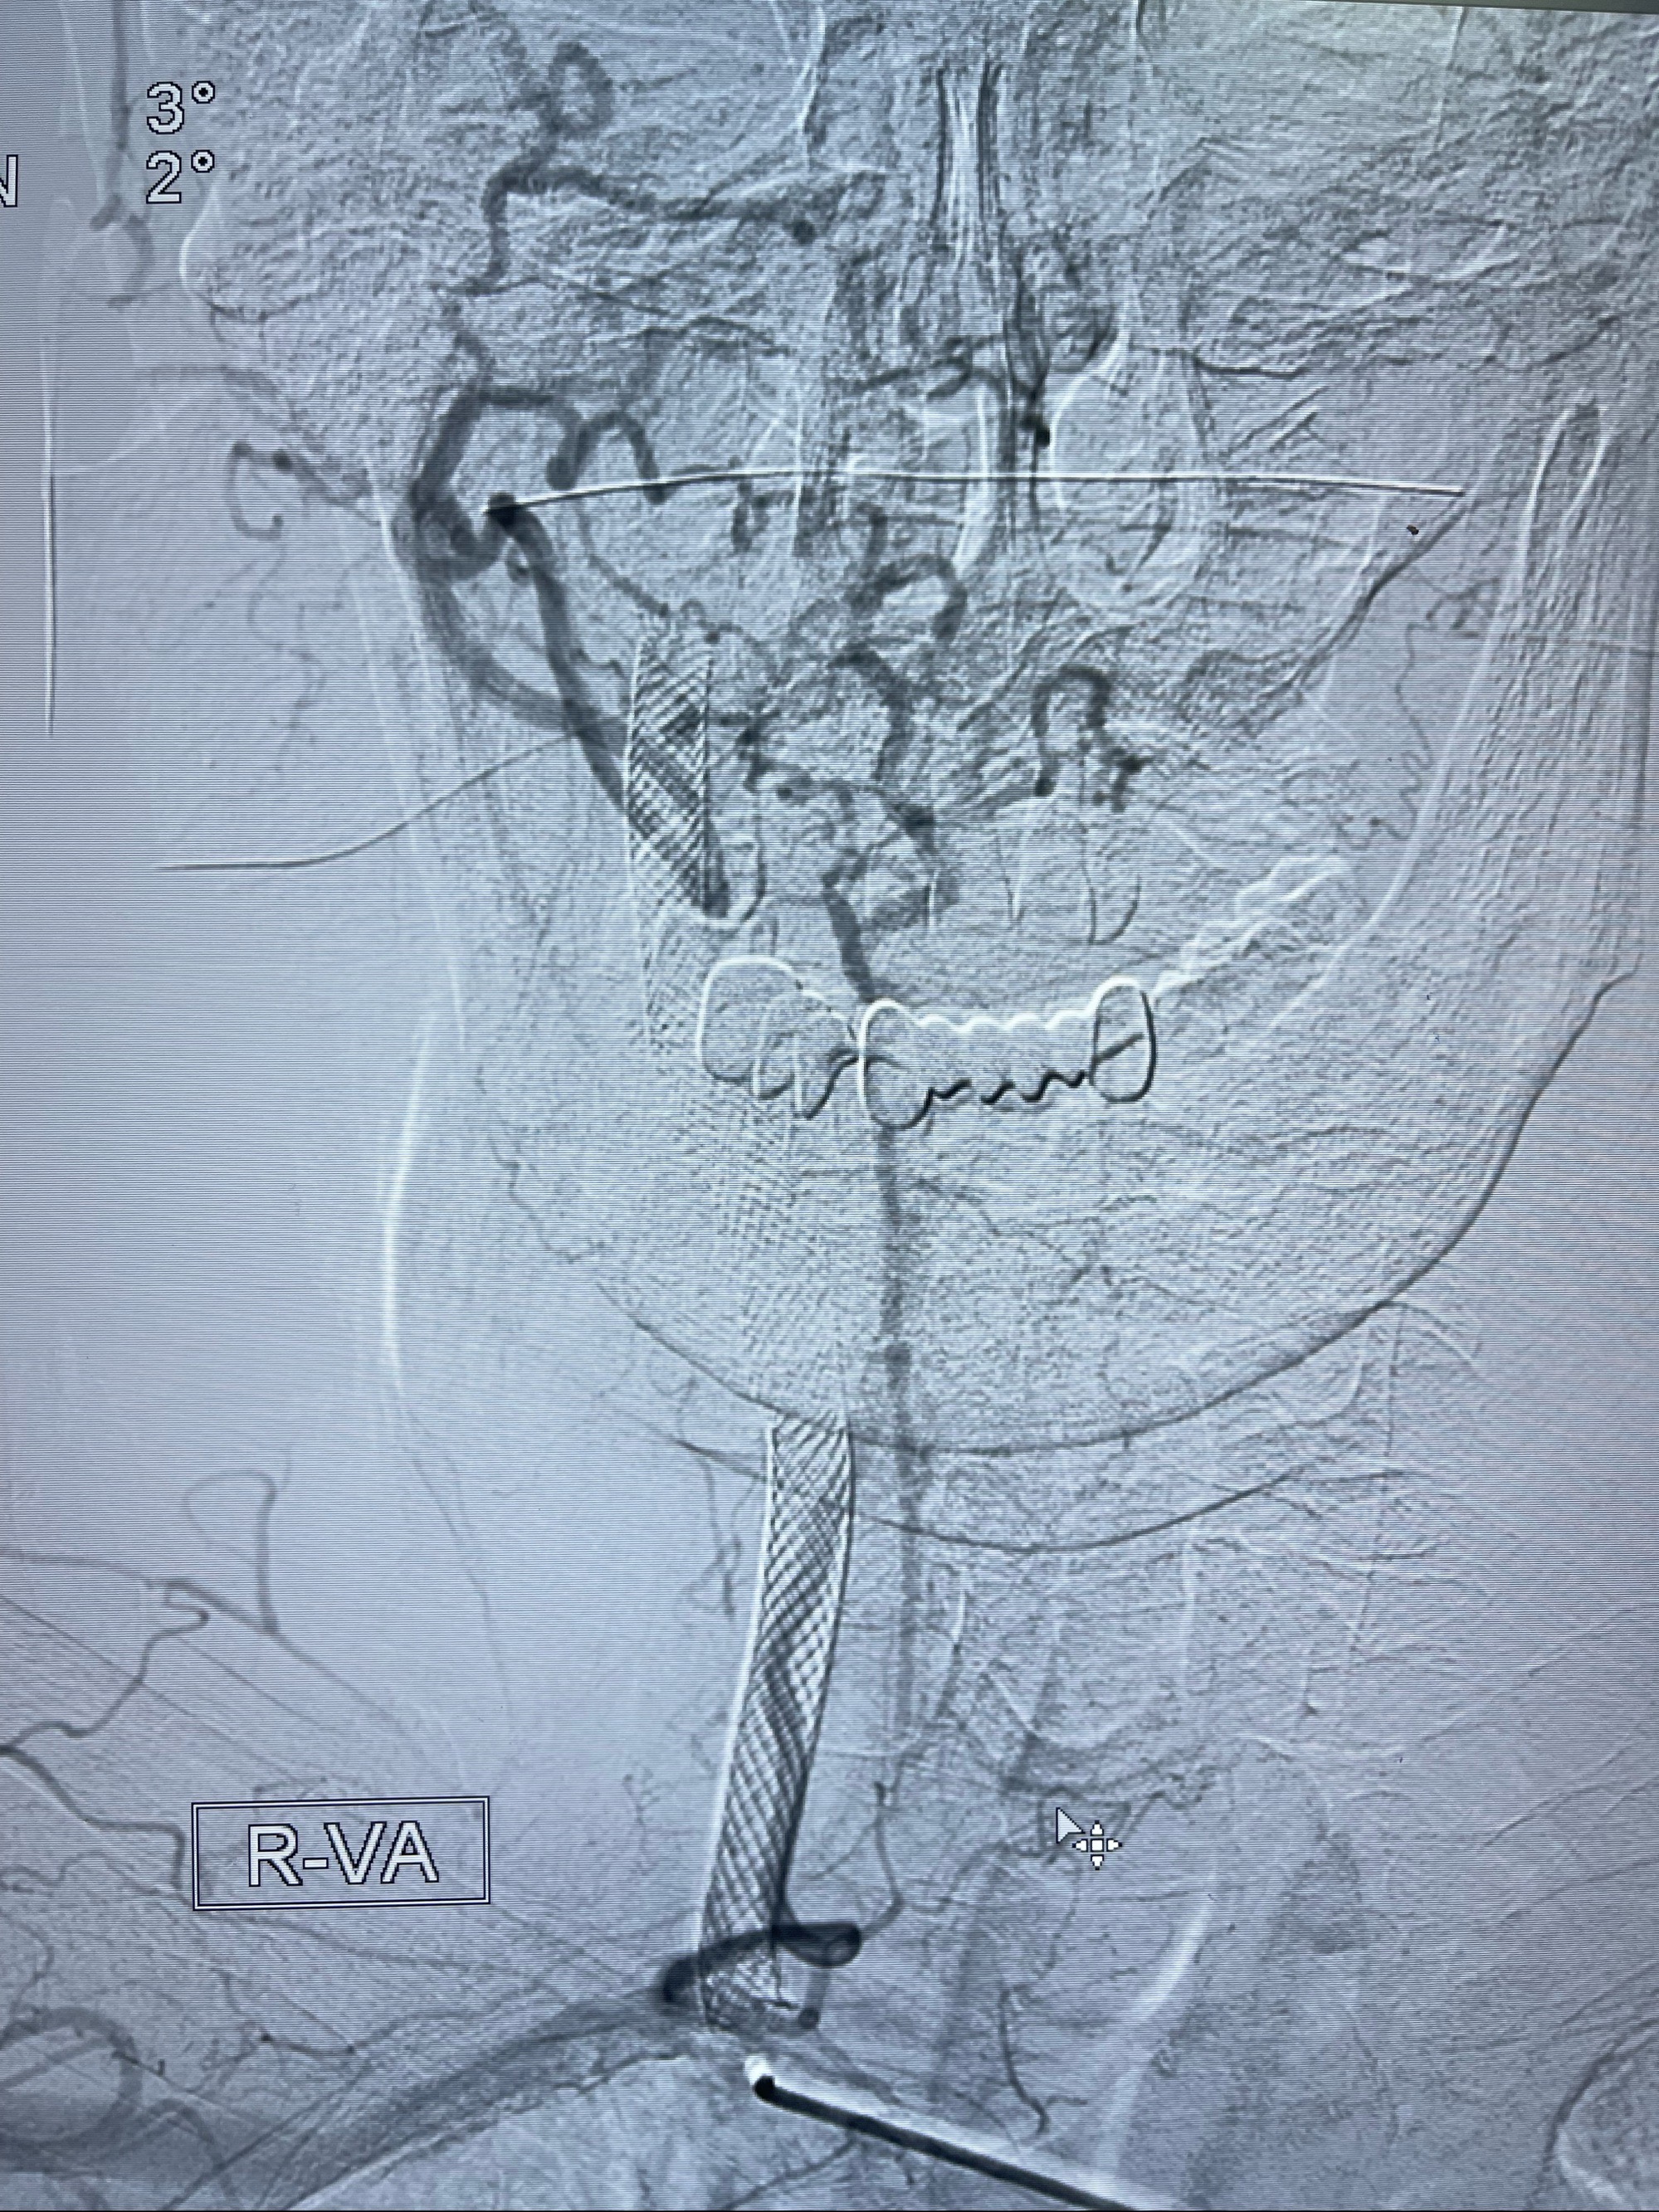

重新行“路径图”,支架导管在微导丝引导下超选择性插入至右侧颈内动脉眼段,4.5-50mmLeo支架释放,远心端位于海绵窦段,近心端位于岩骨段狭窄段以近

即刻造影显示支架贴壁佳

路径图下,5.5-50mmLeo支架导管在微导丝引导下超选择性插入远段Leo支架内

两枚支架部分重叠

多次确认支架位置及打开贴壁情况

支架完全打开,近心端位于原颈动脉支架远心端内

麻醉苏醒佳,遵嘱活动!

术后给予替罗非班300ug/h维持,序贯阿司匹林100mg➕泰嘉75mg口服